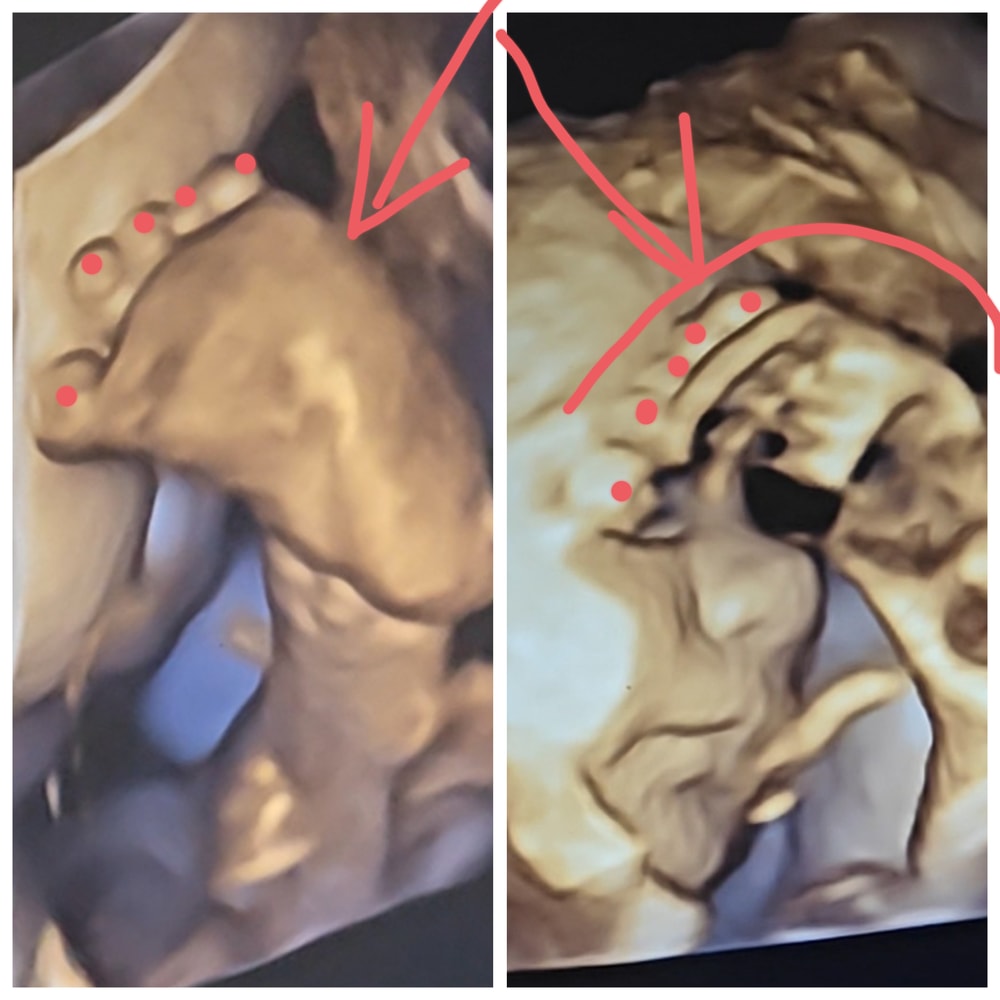

Живот (29-31 неделя) + 4d УЗИ, 31+0

Детонька переместился в головное предлежание и аккуратно сложился пополам. Упирается ногами в матку, отжимая себе немного пространства около лица (а также закрывается ими от датчика, традиция такая😁).

Посему у меня 50+ фото его сладкой левой пяточки:

И всего 1 гифка, как под этой пяточкой он открывает глазки и радуется, что снова потроллил мать и доктора с ненавистным датчиком😁: